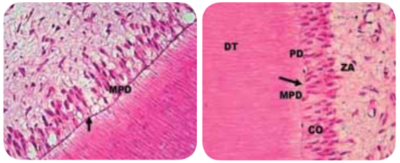

Preparo com CVDentus: Sem danos à membrana pulpo-dentinária. Preservação dos odontoblastos (CO), dentida tubular (DT), pré-dentina (PD) e zona acelular (ZA).